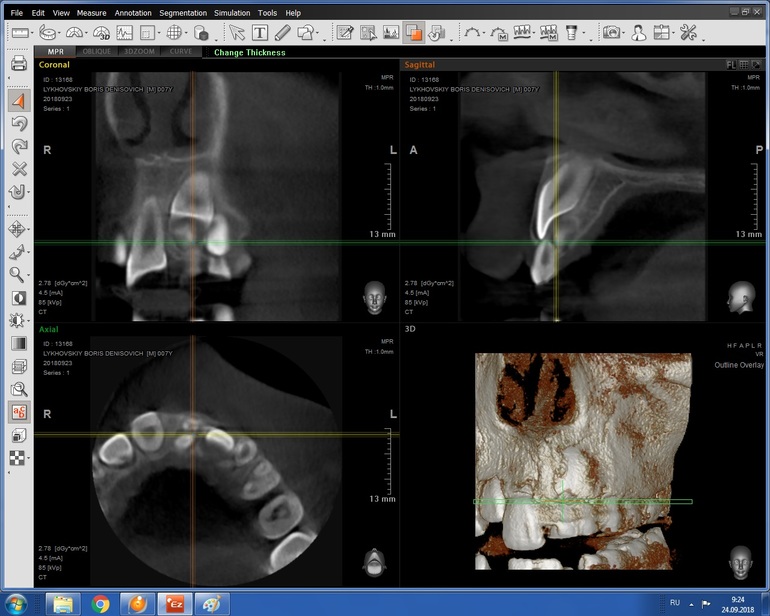

Здравствуйте! Сделали КТ,не с первого раза и не со второго, увы. Поэтому у врача еще небыли. А Вы по КТ сможете подсказать,что у нас и к чему готовиться? Была бы очень признательна!

Я прочитала, КТ всегда делается, если есть подозрение на сверхкомплектные зубы. Без КТ никто в челюсть не полезет удалять что-то. Про брекеты нам никто не говорил, Анна :)

Спасибо, наверное стоит съездить. Насчёт КТ - Вы не поняли, его нужно сделать чтобы подтвердить наличие сверхкомплектные зубов и то, насколько они мешают коренному. Именно на основании КТ принимают решение об удалении сверхкомплектных.

КТ это обязательно при сверхкомплектах, далее решают ортодонт и хирург какими методами и как их убирать. Бывает вытягивают брекетами , бывает убирает хирург, но когда , в каком возрасте это делать будет ясно по КТ.